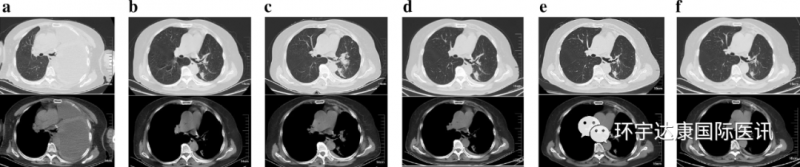

国内IV期肺癌患者徐女士,基因检测显示NCOR2-NTRK1融合,成功入组拉罗替尼在国内的临床试验,成为了国内首批吃螃蟹的幸运儿,免费接受这款药物的治疗,每年剩下了超260万的治疗费!更惊喜的是,这款药物真的让她创造了生存的奇迹!2020年3月,治疗6个月时,CT扫描显示徐女士的部分病灶明显缩小甚至消失了!截至文献发表时,徐女士依然接受拉罗替尼的治疗,状态良好。(注:为保护患者隐私,文中均为化名)